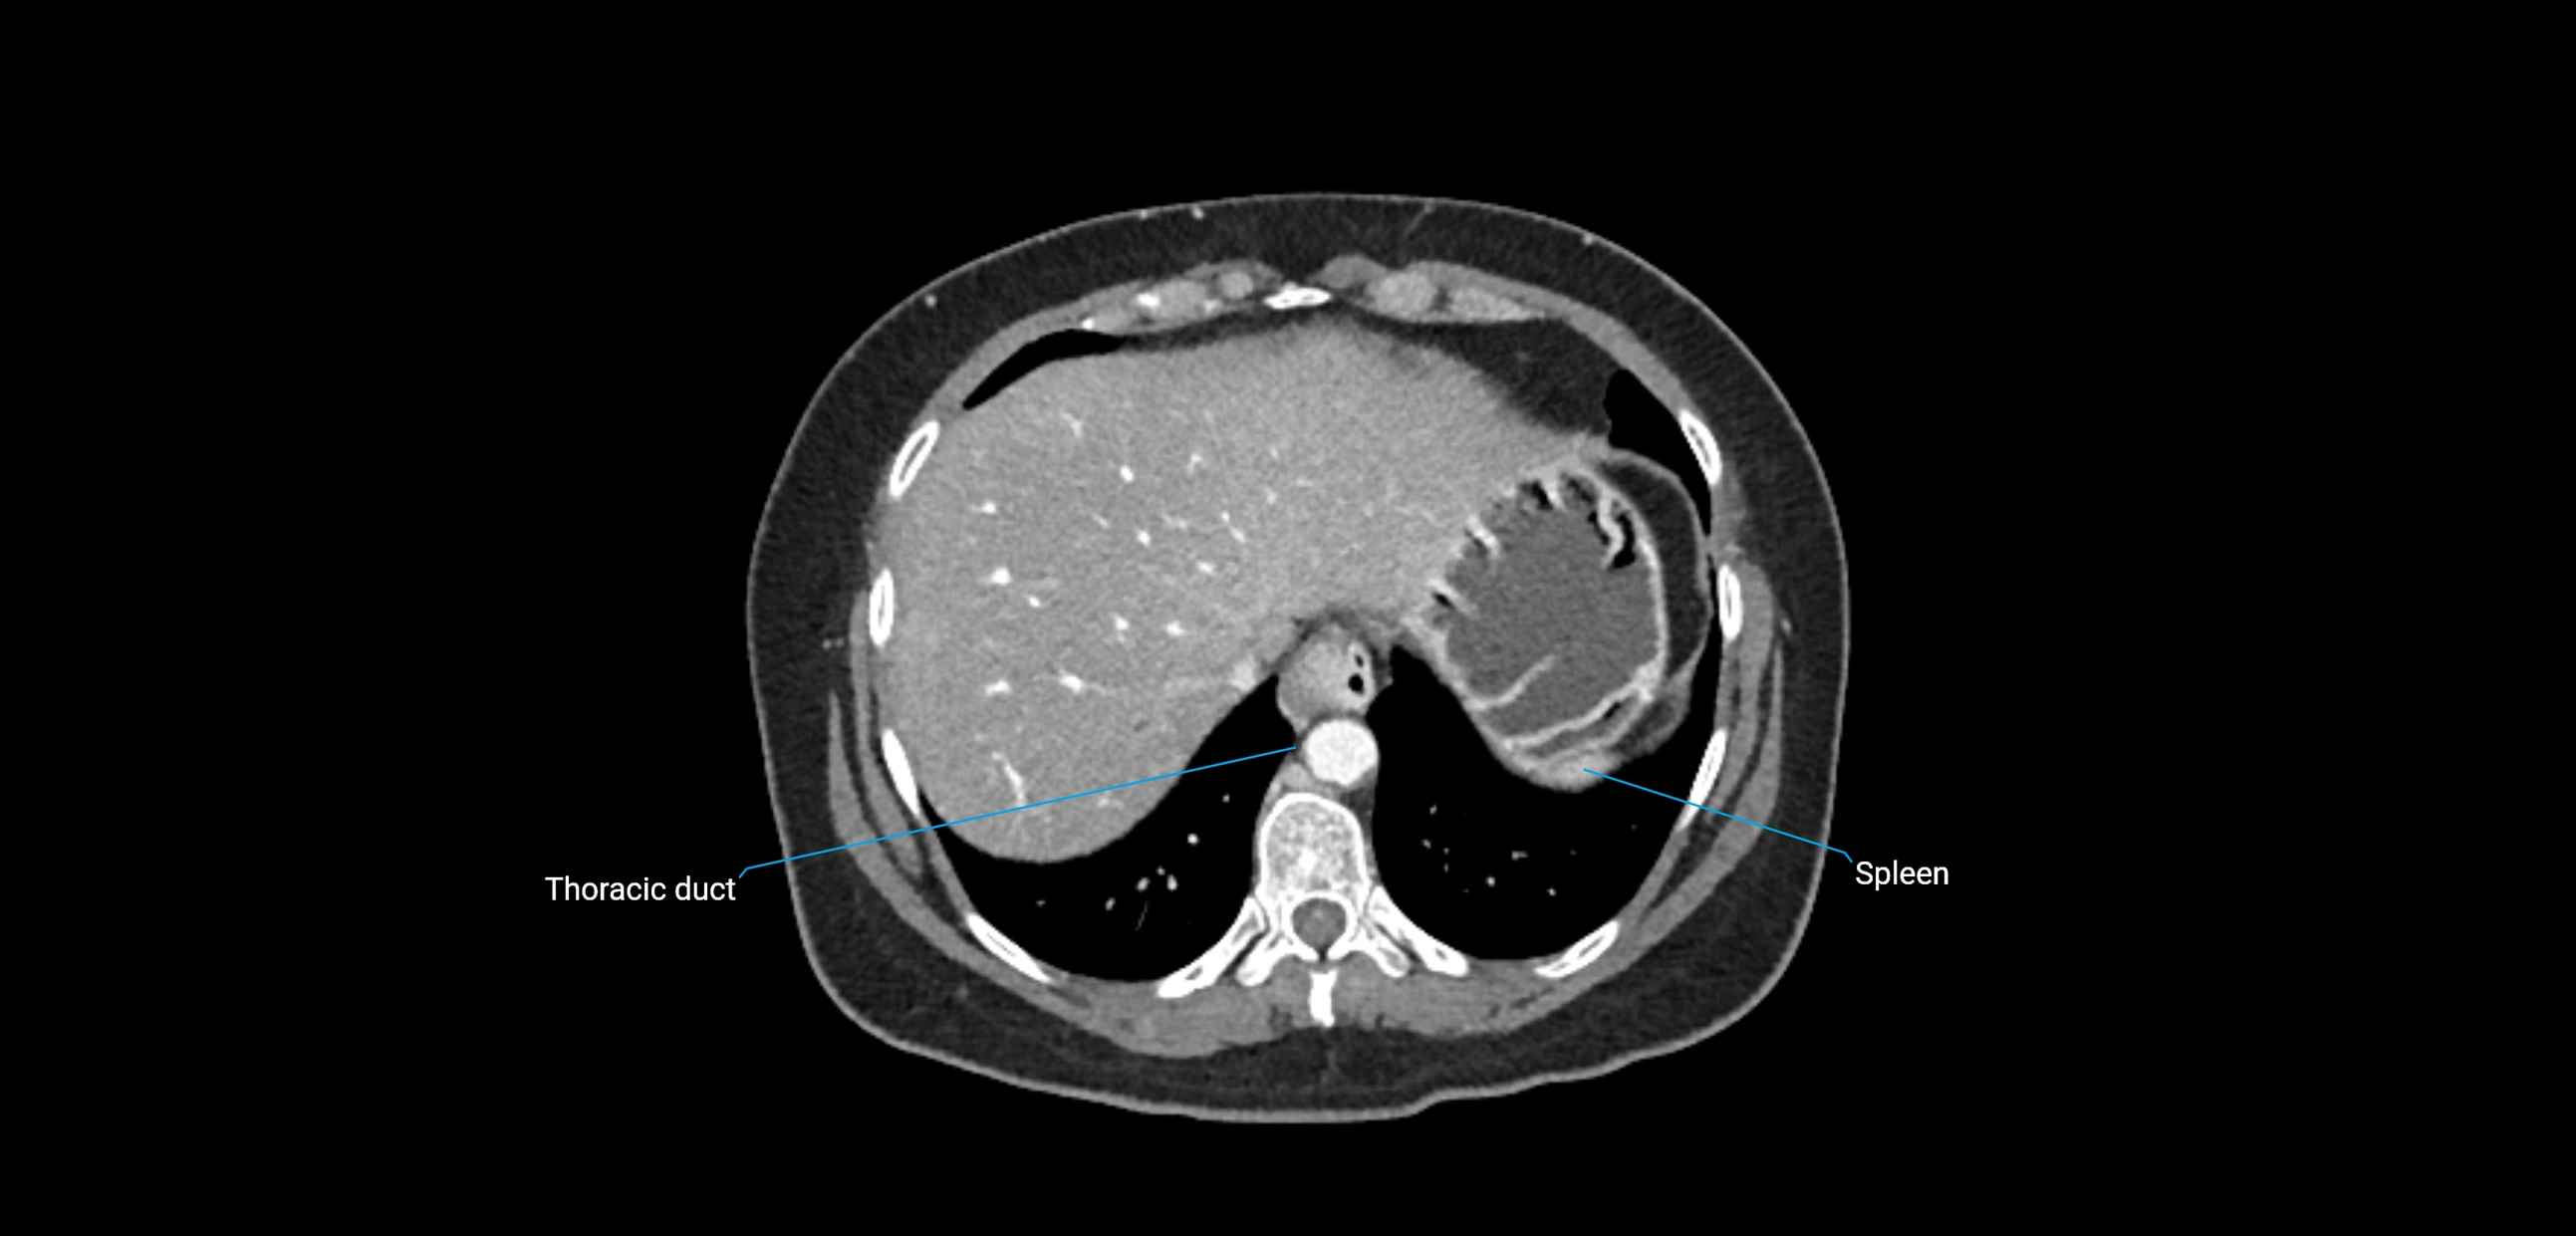

The lateral aortic lymph nodes (also called para-aortic lymph nodes) are a major group of retroperitoneal lymph nodes located along the abdominal aorta and its branches. They lie between the diaphragmatic crura superiorly and the bifurcation of the aorta at L4 inferiorly.

These nodes receive lymph from a wide range of abdominal and pelvic structures. Specifically, they drain lymph from the kidneys, suprarenal glands, gonads (testes/ovaries), uterus, uterine tubes, and pelvic organs, before converging into the lumbar lymphatic trunks, which terminate in the cisterna chyli → thoracic duct.

• Provide a major pathway to the cisterna chyli and thoracic duct